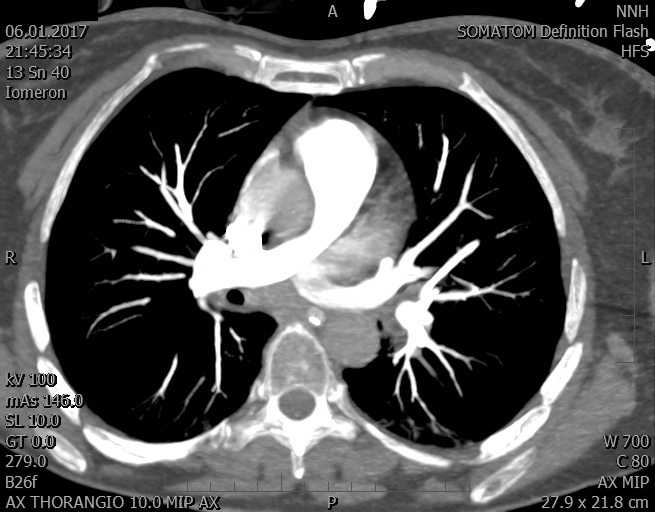

Video 1 - Akutní koronarografie prokázala normální nález na věnčitých tepnách s výjimkou suspekce na lehký spasmus na pravé koronární tepně.Echokardiograficky byla zjištěna těžká dysfunkce dilatované levé komory s nezvětšenou pravou komorou (video 2).

Video 2 - Echokardiograficky byla zjištěna těžká dysfunkce dilatační levé komory s nezvětšenou pravou komorou.Pro nejasnou příčinu zástavy jsme provedli i vyšetření výpočetní tomografií (CT), které vyloučilo plicní embolizaci (série 1 - soubory na konci článku). V den přijetí při přetrvávající oběhové nestabilitě byla nemocná opakovaně defibrilována pro fibrilaci komor se stabilizací rytmu po podání amiodaronu a mesocainu. Dle hemodynamických měření se jednalo o těžký kombinovaný šok. Vstupní laboratorní vyšetření bylo bez větších pozoruhodností. Posléze jsme doplnili anamnézu od příbuzných a zjistili, že pacientka užila do dvou hodin před srdeční zástavou první tabletu amoxicilinu na lehký respirační infekt. Při nevýtěžnosti vstupních vyšetření a nových anamnestických informacích jsme doplnili 14 hodin po kolapsu vyšetření koncentrace tryptázy v séru, která byla extrémně zvýšena (tabulka 2), což nás vedlo k podezření na anafylaxi.